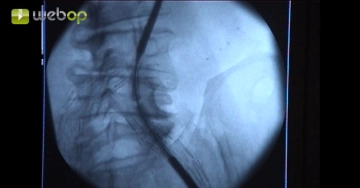

Die Freilegung der linken Leiste wurde in diesem Fall einer Punktion vorgezogen, weil nach Voroperation starke Vernarbungen in der Leiste vorlagen und das Trägersystem ein großes Kaliber besitzt. Nach Anschlingen der A. femoralis communis zentral und peripher wird eine Punktion in Seldinger-Technik vorgenommen. Über den Führungsdraht wird eine 7-F-Schleuse eingeführt. Gabe von 5000 IE Heparin-Kochsalzlösung lokal in das Gefäß.

Um eine Gefäßperforation zu vermeiden darf der steife Führungsdraht wegen des starken Kinkings der linken Beckenstrombahn und der papierdünnen Gefäßwände nicht zu weit vorgeschoben werden.